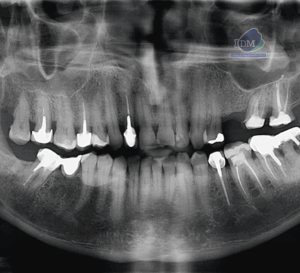

Paciente masculino de 81 años acudió al Instituto de Diagnóstico Maxilofacial (IDM) para una evaluación imagenológica general. En la radiografía panorámica (Figura 1) se identificó,